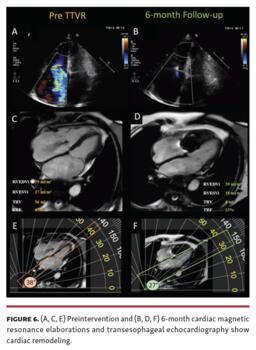

The preprocedural cardiac magnetic resonance (CMR) showed a right ventricular end-diastolic volume index (RVEDi) of 79 mL/m2, right ventricular end-systolic volume index (RVESi) of 27 mL/m2, tricuspid regurgitant volume (TRV) of 56 mL, and tricuspid regurgitant fraction (TRF) of 67% (Figure 3). Due to the patient's history of breast cancer radiotherapy and high surgical risk, the heart team preferred a transcatheter approach as the treatment option. The first TriClip (Abbott Vascular) was successfully implanted in the anteroseptal commissure, determining annulus size reduction and the subsequent necessity of transesophageal echocardiographic projection change to assess the result due to acute reshaping (Figure 4 and Figure 5; Video Series). A second TriClip was implanted in the anteroseptal commissure, highlighting the changes in the valvular plane and cardiac axis (Video Series). Residual TR was trivial (Video Series). The acute remodeling was confirmed at the CMR follow-up (Figure 6), with significant volume and TR reductions (RVEDi, 39 mL/m2; RVESi, 18 mL/m2; TRV, 8 mL; and TRF, 23%).